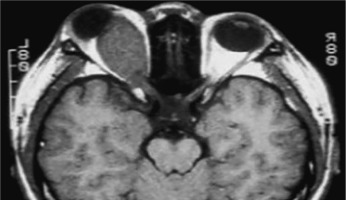

Neurofibromatosis type 1 (von Recklinghausen disease) is a phakomatosis caused by a mutation in the NF1 gene located on chromosome 17q11.2. This gene encodes the protein neurofibromin, which is responsible for regulating cell division and proliferation [5, 6]. The traditional designation of these abnormalities as von Recklinghausen disease is now considered largely historical. The disease has an estimated prevalence of approximately 1 : 3,500 live births and affects 1 : 4,000 to 1 : 5,000 individuals in the general population [4, 8, 9]. Neurofibromatosis type 1 is inherited in an autosomal dominant manner, although more than half of cases occur sporadically, representing new mutations [9]. In most children, the new mutation is inherited from a parent. The risk that a child of an affected parent will develop neurofibromatosis type 1 is approximately 50%. A characteristic feature of the disease is the appearance of pigmented patches on the skin, referred to as café-au-lait spots. The presence of at least five to six such spots, covering any region of the child’s body, is indicative of the disease. Freckles and areas of hyperpigmentation are also observed in regions with limited light exposure, such as the axillae, groin, and beneath the breasts in women (Crowe’s sign). Also, diffuse neurofibromas occur in the skin, brain, and spinal cord. The primary distinguishing feature of changes in the eyeball is the presence of Lisch nodules on the iris and other characteristic ocular features of this syndrome [10–12]. Lisch nodules arise as a result of developmental disturbances and uncontrolled divisions of mast cells and pigment epithelium forming the outer surface of the iris [8, 10, 11] (Figure 4). They are a consequence of damage to the choroidal melanocytes and, histologically, correspond to melanocytic hamartomas of the iris. A diagnosis is warranted by the presence of at least two Lisch nodules. The role of solar radiation in their development remains controversial [12]. Lisch nodules are visible on slit-lamp examination as small, vascularized, elevated structures of the iris, measuring 0.1 mm to 2 mm in size, in various shades of brown. Their position within the iris crypts can occasionally make them difficult to detect. Lisch nodules occur in 10% to 90% of children with this syndrome, and their number increases with age. The nodules do not affect visual acuity, but when they are numerous and asymmetrically distributed between the eyes, they may lead to cosmetic concerns. Glaucoma in neurofibromatosis type 1 coexists in approximately 50% of cases with neurofibromas of the upper eyelid and hemifacial atrophy. Congenital glaucoma results from developmental defects in the anterior chamber angle during embryogenesis. Glaucoma can also be secondary to angle closure caused by phakomata of the iris and ciliary body. Fibrovascular proliferations imply the development of neovascular glaucoma. Optic nerve glioma occurs in 15% of children with neurofibromatosis type 1. The disease may also be associated with other central nervous system tumors, such as neurofibromas or meningiomas. Optic nerve glioma is typically unilateral and presents in approximately 70% of cases before the age of 10. It occurs more frequently in females, with an incidence ranging from 25% to 50% (Figure 5). The symptoms of glioma progress slowly. The initial manifestation is typically painless and gradually progressive proptosis. Due to its slow onset, this change may go unnoticed by those in close daily contact with the child – such as parents or caregivers. Quite often, it is an outsider – someone who has not seen the child for an extended period – who first notices the proptosis. As the glioma advances, additional symptoms such as visual disturbances, reduced visual acuity (potentially leading to complete blindness), and strabismus begin to emerge, eventually drawing the attention of those closest to the child to the deterioration of their visual system. The growth of the tumor is accompanied by swelling of the optic disc, followed by its atrophy. Pulsatile exophthalmos, which may arise as a consequence of conditions associated with neurofibromatosis type 1, often has a silent, asymptomatic course, without orbital bruits, due to a defect in the greater wing of the sphenoid bone and herniation of brain tissue into the sphenoid sinus and orbit. Other pathological changes that occur during the development of optic nerve glioma include plexiform neurofibroma of the eyelids with associated ptosis and dysplasia of the orbital bone, leading to compression of the optic nerve. Pigmented uveal nevi, increased incidence of choroidal melanoma, and retinal glial hamartomas are observed. Refractive errors can occur in both neurofibromatosis type 1 and type 2 [13]. Other rare ocular manifestations include prominent cor-neal nerves, congenital eversion of the iris pigment epithelium, iris nevi or hamartomas, and generalized choroidal thickening.

The diagnosis of phakomatosis is based on a thorough medical history, which includes the presence of phakomatosis-type lesions or other systemic disorders in the family, as well as symptoms reported by the child or their parents. Ophthalmologic examination includes all elements of the clinical assessment, performed under local or general anesthesia, depending on the child’s age. Important diagnostic tests include genetic analyses [17]. Prenatal diagnosis is possible through molecular testing of amniotic or chorionic cells. Genetic counselling plays a crucial role in supporting informed reproductive decision-making for patients and at-risk family members [18, 19]. Imaging examinations are also important in the diagnostic work-up. These include magnetic resonance imaging (MRI) and computed tomography (CT) of organs and systems potentially affected by the disease process – such as the head and brain – as well as ocular and orbital ultrasound, chest X-ray, electrocardiography (ECG), electroencephalography (EEG), and other examinations required for an accurate diagnosis. An essential part of diagnosis and therapy involves consultations from other medical specialties and interdisciplinary collaboration.